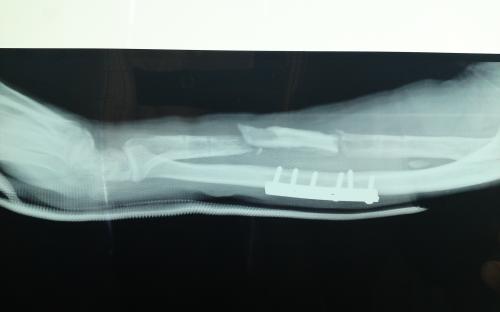

Άντρας 21 ετών υπέστη διπολικό κάταγμα της κερκίδας και κάταγμα της ωλένης, που αντιμετωπίστηκε σε περιφεριακό νοσοκομείο. 9 μήνες μετά διαπιστώθηκε ψευδάρθρωση της κερκίδας με οστικό απόλυμα 6,5 εκ. Αντιμετωπίστηκε με τη χρήση αγγειούμενης περόνης, η οποία γεφύρωσε το οστικό έλλειμμα της κερκίδας.